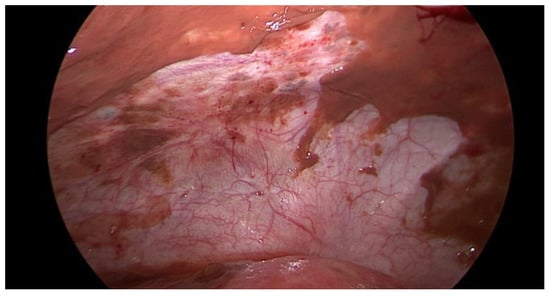

Data collection: The patients’ backgrounds, clinical symptoms at admission, sonographic and laboratory assessment, as well as intraoperative findings were recorded. Patient demographic data included age, menopausal status, presence of dysmenorrhea, history of endometriosis surgery, and use or non-use of hormonal downregulation therapy for endometriosis. Pre-operative laboratory tests included white blood cell (WBC) count, serum C-reactive protein (CRP) level, and serum CA125 level, and all patients underwent transvaginal sonography (Figure 1) on admission as part of the emergency diagnostic assessment. The maximal diameter and the location of the endometriomas were noted. The intraoperative findings included the location of the ruptured endometriomas (Figure 2 and Figure 3), the presence and classification of endometriosis according to the rASRM [16] and #ENZIAN [17] systems, and, lastly, total blood loss.

Figure 3. Intraoperative laparoscopic display of anterior pelvic spillage in a patient with concomitant peritoneal endometriosis.